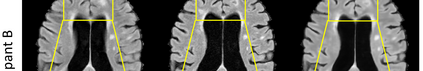

Multiple Sclerosis (MS) is a chronic progressive neurological disease characterized by the development of lesions in the white matter of the brain. T2-fluid-attenuated inversion recovery (FLAIR) brain magnetic resonance imaging (MRI) provides superior visualization and characterization of MS lesions, relative to other MRI modalities. Longitudinal brain FLAIR MRI in MS, involving repetitively imaging a patient over time, provides helpful information for clinicians towards monitoring disease progression. Predicting future whole brain MRI examinations with variable time lag has only been attempted in limited applications, such as healthy aging and structural degeneration in Alzheimer's Disease. In this article, we present novel modifications to deep learning architectures for MS FLAIR image synthesis, in order to support prediction of longitudinal images in a flexible continuous way. This is achieved with learned transposed convolutions, which support modelling time as a spatially distributed array with variable temporal properties at different spatial locations. Thus, this approach can theoretically model spatially-specific time-dependent brain development, supporting the modelling of more rapid growth at appropriate physical locations, such as the site of an MS brain lesion. This approach also supports the clinician user to define how far into the future a predicted examination should target. Accurate prediction of future rounds of imaging can inform clinicians of potentially poor patient outcomes, which may be able to contribute to earlier treatment and better prognoses. Four distinct deep learning architectures have been developed. The ISBI2015 longitudinal MS dataset was used to validate and compare our proposed approaches. Results demonstrate that a modified ACGAN achieves the best performance and reduces variability in model accuracy.